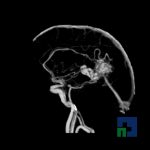

Examinare de rutină cerebrală, nativ și cu substanță de contrast (SDC) pentru diagnosticul:

- Accidentelor vasculare cerebrale ischemice sau hemoragice

- Tumorilor cerebrale

În cazul traumatismelor cranio-cerebrale:

- Diagnosticul edemului cerebral, a contuziei cerebrale, a leziunilor axonale difuze edematoase/hemoragice, a dilacerării cerebrale, a hematomului intraparenchimatos posttraumatic, a hematoamelor subdurale/extradurale (acute, subacute, cronice), a hemoragiei intraventriculare, a hemoragiei subarahnoidiene

- Diagnosticul traumatismelor de bază de craniu

- Diagnosticul fistulei LCR

- Diagnosticul herniilor cerebrale